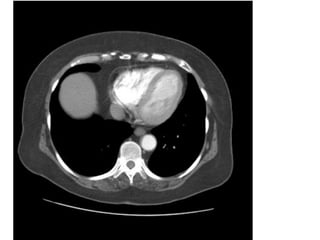

• Chụp CT ngực không cản quang

• Chụp CT ngực có cản quang

XEM HÌNH KHÔNG CHÍCH CHẤT TƯƠNG PHẢN (CE-) TRƯỚC

RỒI MỚI ĐẾN HÌNH CÓ CHÍCH CHẤT TƯƠNG PHẢN (CE+)